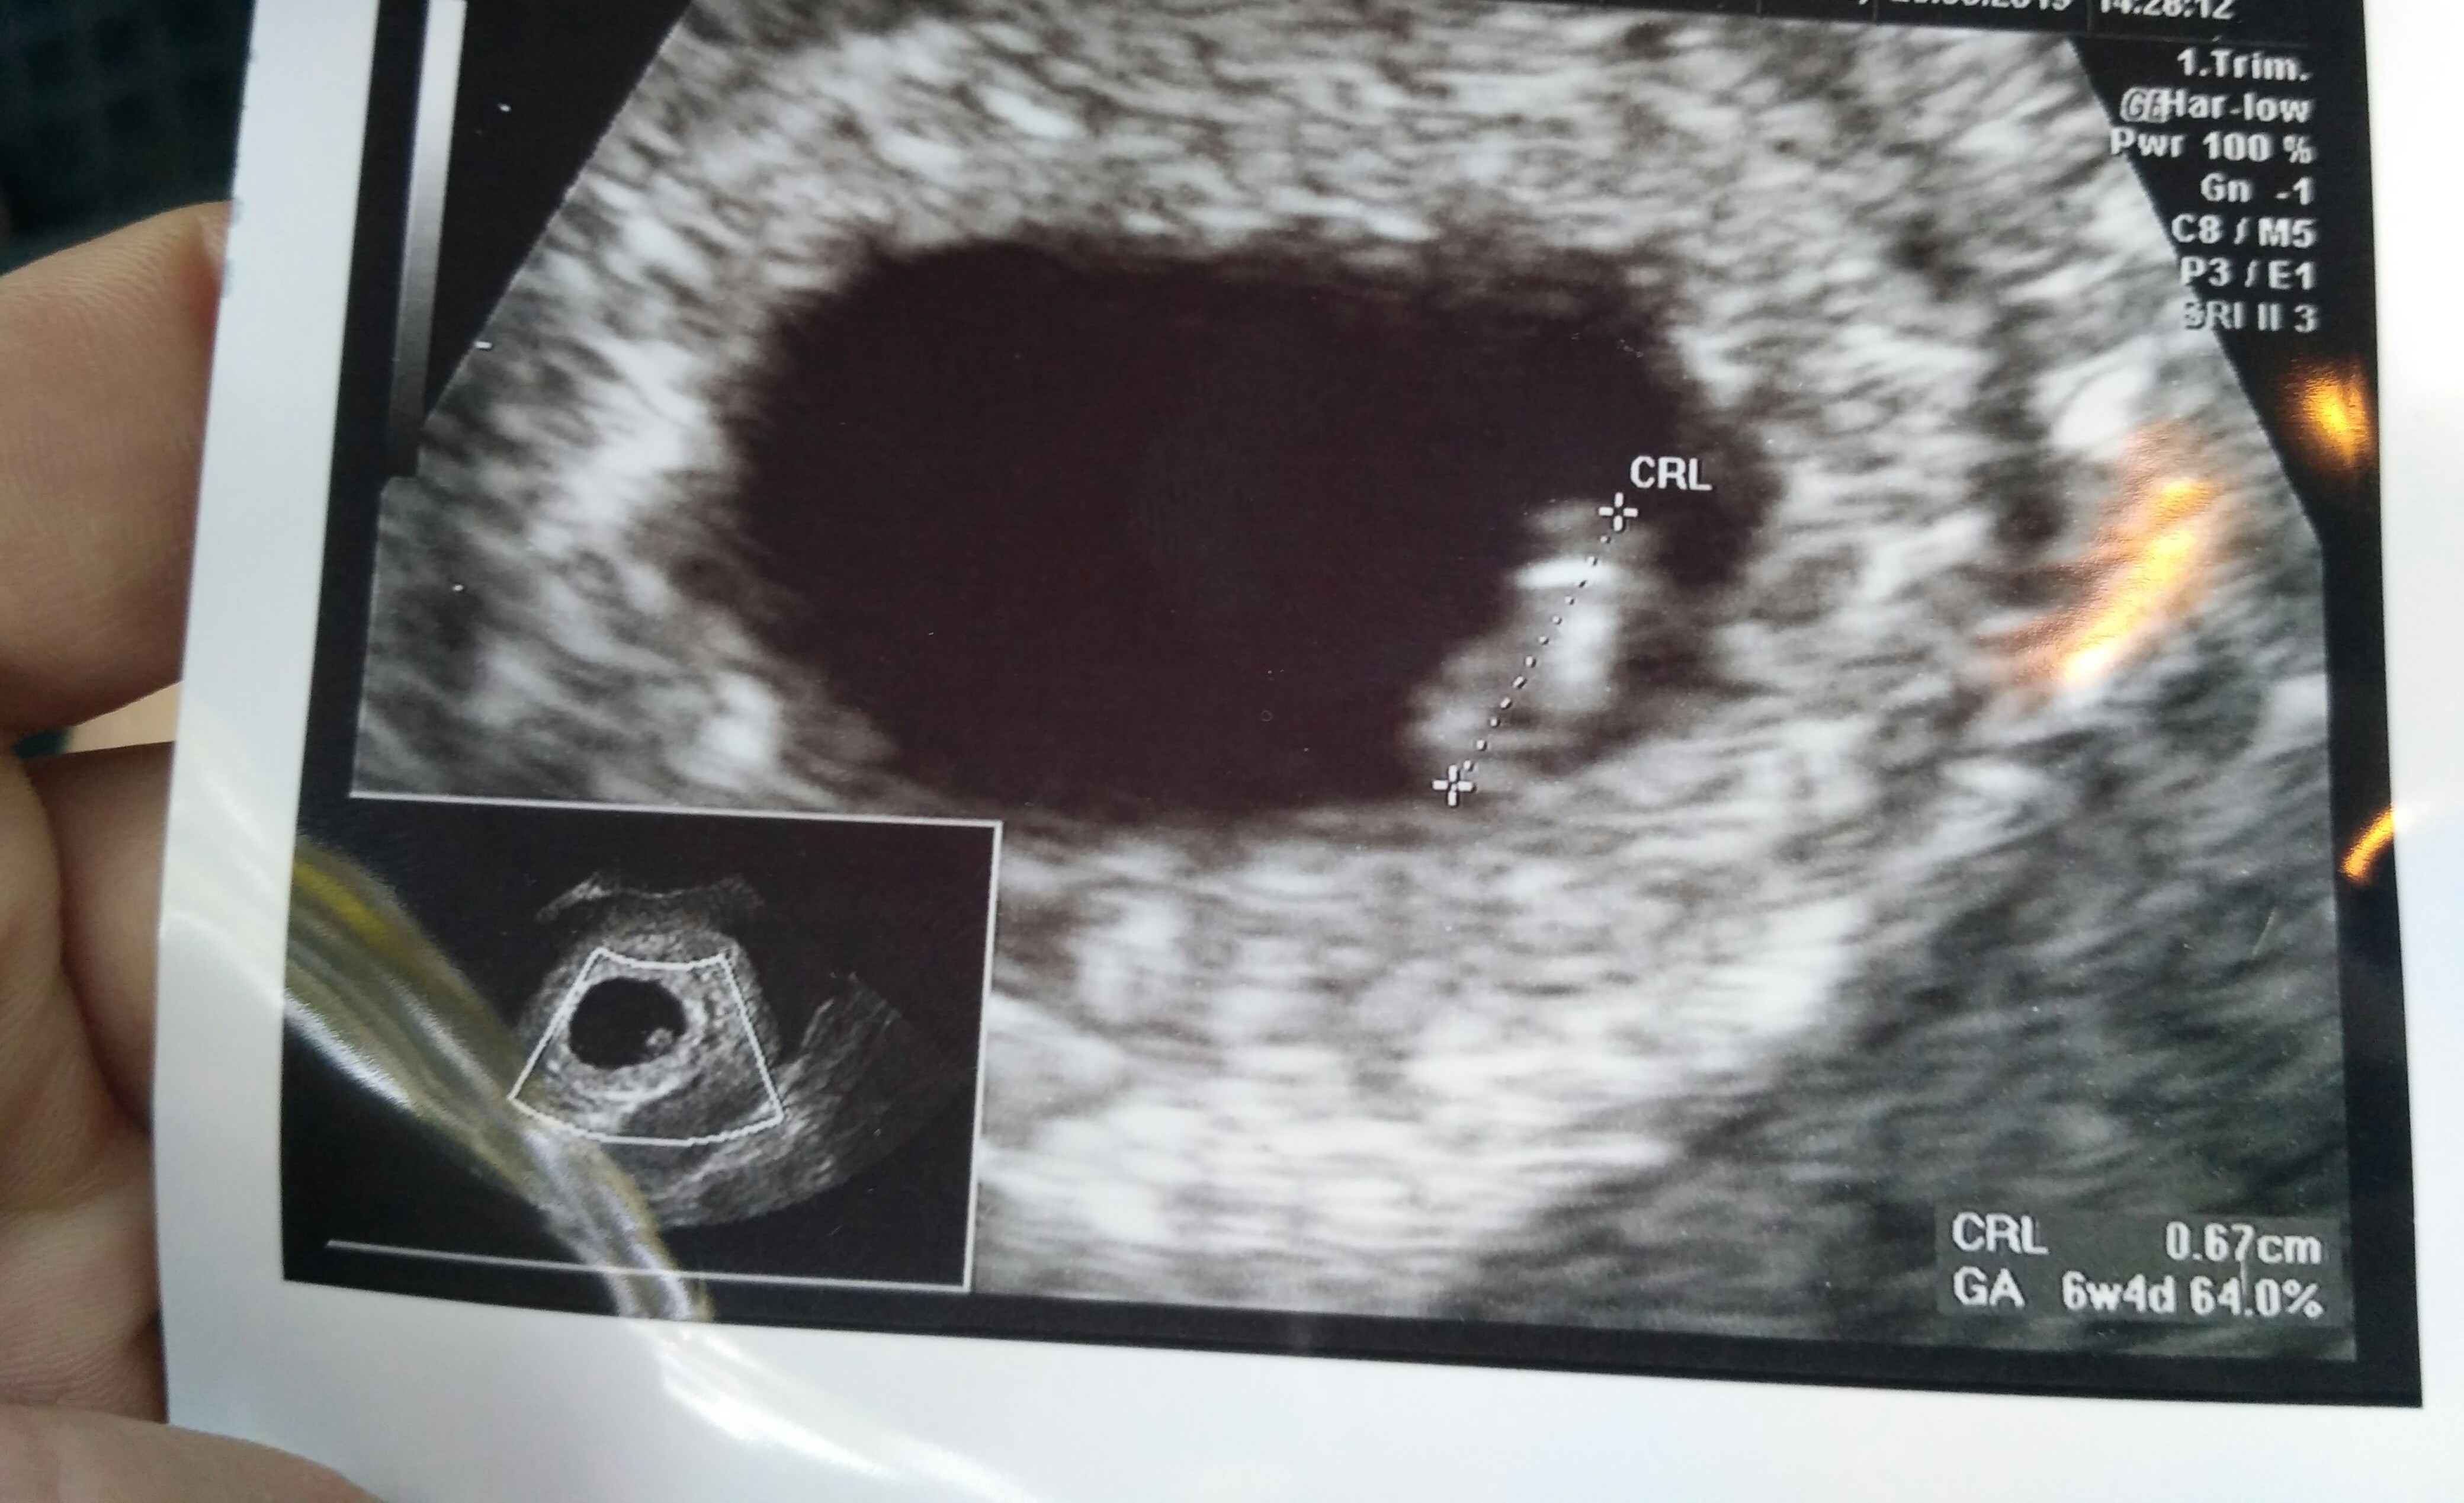

A u mnie według tej metody bo się nie znam ?Super wieści!!!I syn według metody Ramziego [emoji16][emoji16][emoji16]

No chłopak ewidentnie [emoji16]A u mnie według tej metody bo się nie znam ?![]()